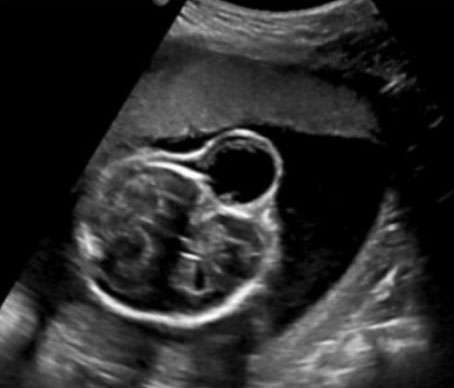

A routine fetal ultrasound assessment performed at 19 weeks’ gestation revealed right lateral encephalocele (Figure 1), large right cleft lip and palate with the defect expanding to the right eye socket, left lower extremity edema, and bilateral rocker-bottom feet (Figure 2, Figure 3, Figure 4). The patient underwent an amniocentesis at 20 weeks gestation that revealed normal male karyotype and normal microarray, without any maternal cell contamination. Repeat ultrasound at 23 weeks gestation showed previous anomalies with appearance of a thick right lateral amniotic band spanning the full length of the skull and facial defects as well as bilateral clenched fists (Figure 5). Fetal echocardiogram done at that time was without any evidence of structural cardiac abnormalities. She underwent extensive consultation in regard to ABS and outcomes, with plans for close follow-up. She presented at 26 weeks gestation for her scheduled growth scan reporting decreased fetal movement. She was diagnosed with intrauterine fetal demise measuring in the 9th percentile with an estimated fetal weight of 768 grams. She was admitted for induction of labor and went on to have an uncomplicated vaginal delivery. After delivery, fetal examination revealed profound midfacial deformities, brachydactyly, and placental adhesions. Placental pathology significant for a 20.7 cm long three vessel, peripherally inserted, umbilical cord with amnion constriction near placental insertion. Fetal membranes displayed features of amnion/chorion disruption as well as thickened bands of chorionic connective tissue and extraembryonic celom between the amnion and the chorion. These findings were somewhat difficult to fully discern due to the breakdown of fetal tissue after the intrauterine fetal demise.

Figure 3: Transverse view of amniotic band contact with fetal cranium.

Figure 4: Transverse view of lateral encephalocele.

Figure 5: Addition amniotic band contact area.